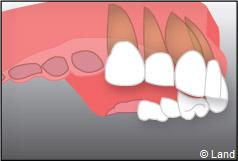

Exemple de 3 dents manquantes remplacées par 3 couronnes sur implants.

Pose des piliers prothétiques et des 3 couronnes scellées.